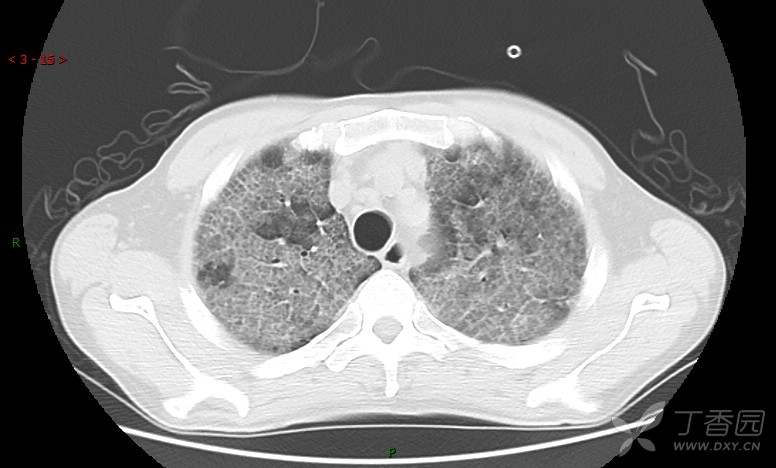

地图+铺路石征=PAP?那升高的CEA怎么说(病例3连发,附其他2例链接)

患者男,42岁,咳嗽半年余,加重伴憋喘2月余。

患者半年余前无明显诱因出现间断咳嗽,干咳为主,偶咳少量黄白痰,剧烈咳嗽或运动后可出现轻度憋喘,无高热、脓臭痰,无胸痛、咯血及晕厥,无低热乏力及盗汗,无心前区压榨感及夜间阵发性呼吸困难,初未在意,未予正规诊治。2月余前患者自觉上述症状较前加重,咳嗽、憋喘明显,黄白色粘痰略有增多,伴有发热,热前伴有畏寒、寒战,体温最高达38.9℃,先后就诊多家医院,入住重症监护室,未行气管插管,考虑“重症肺炎”,给予“美罗培南、复方磺胺甲噁唑”等药物抗感染,“卡泊芬净”抗真菌,并给予“甲泼尼龙”等药物治疗35天,经治疗后症状好转于2018-04-02出院。患者自出院后仅应用中药治疗(具体不详),并给予家庭氧疗,平素仍有间断咳嗽,咳少量黄白色粘痰,活动后憋喘明显,活动耐量差,以卧床为主。

肺内弥漫性网状结节影,PET-CT却无阳性病灶,这是?(附其他2例链接)